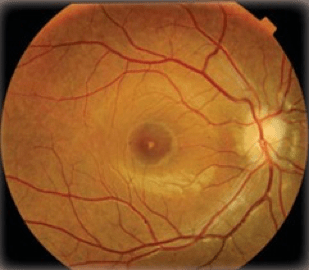

Η ηλιακή ακτινοβολία αποτελείται από υπέρυθρες, υπεριώδεις (UV) και ακτίνες υψηλής ενέργειας που ανήκουν στο ορατό φάσμα (είναι δηλαδή αντιληπτές από εμάς). Οι ακτίνες αυτές προκαλούν βλάβες τόσο στους εξωτερικούς χιτώνες του ματιού, όσο και στον αμφιβληστροειδή χιτώνα στον οποίο απεικονίζεται το είδωλο της εικόνας που βλέπουμε.